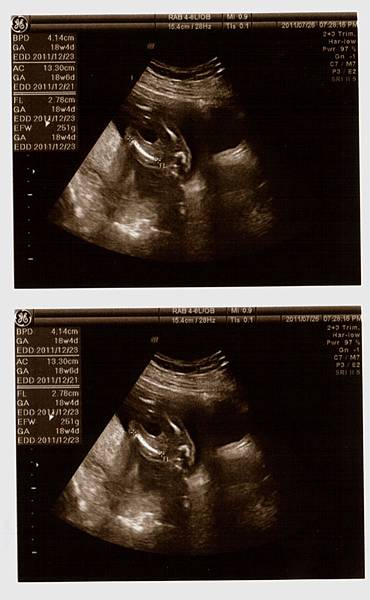

接著,重頭戲來囉,黃醫師幫我照了超音波,躺在床上的我和站在一旁的老公顯得緊張,當我還在思考等一下醫生會告訴我寶寶究竟是男是女之際,思路還來不及轉彎之時,黃醫師就已迅雷不及掩耳的速度告訴我:『這是男寶寶喔!』我驚訝的不得了!還說『怎麼看啊?在哪在哪?』醫生不急不徐地說:『這是寶寶的弟弟,有看到凸出來的,那就是弟弟喔!』天啊,是弟弟啊(說實在,我真想看看老公當時的表情><)接著,醫師告訴我寶寶的頭偏大,看來是個大頭弟,大腿骨普通長(媽媽我還以為他是個長腿男勒!),然後醫師拿著探頭四處看,告訴我寶寶的一切都正常,讓媽咪我放心了許多!

一連串拿了七張超音波照片,還看了4D的超音波,真是超棒的唷!!!